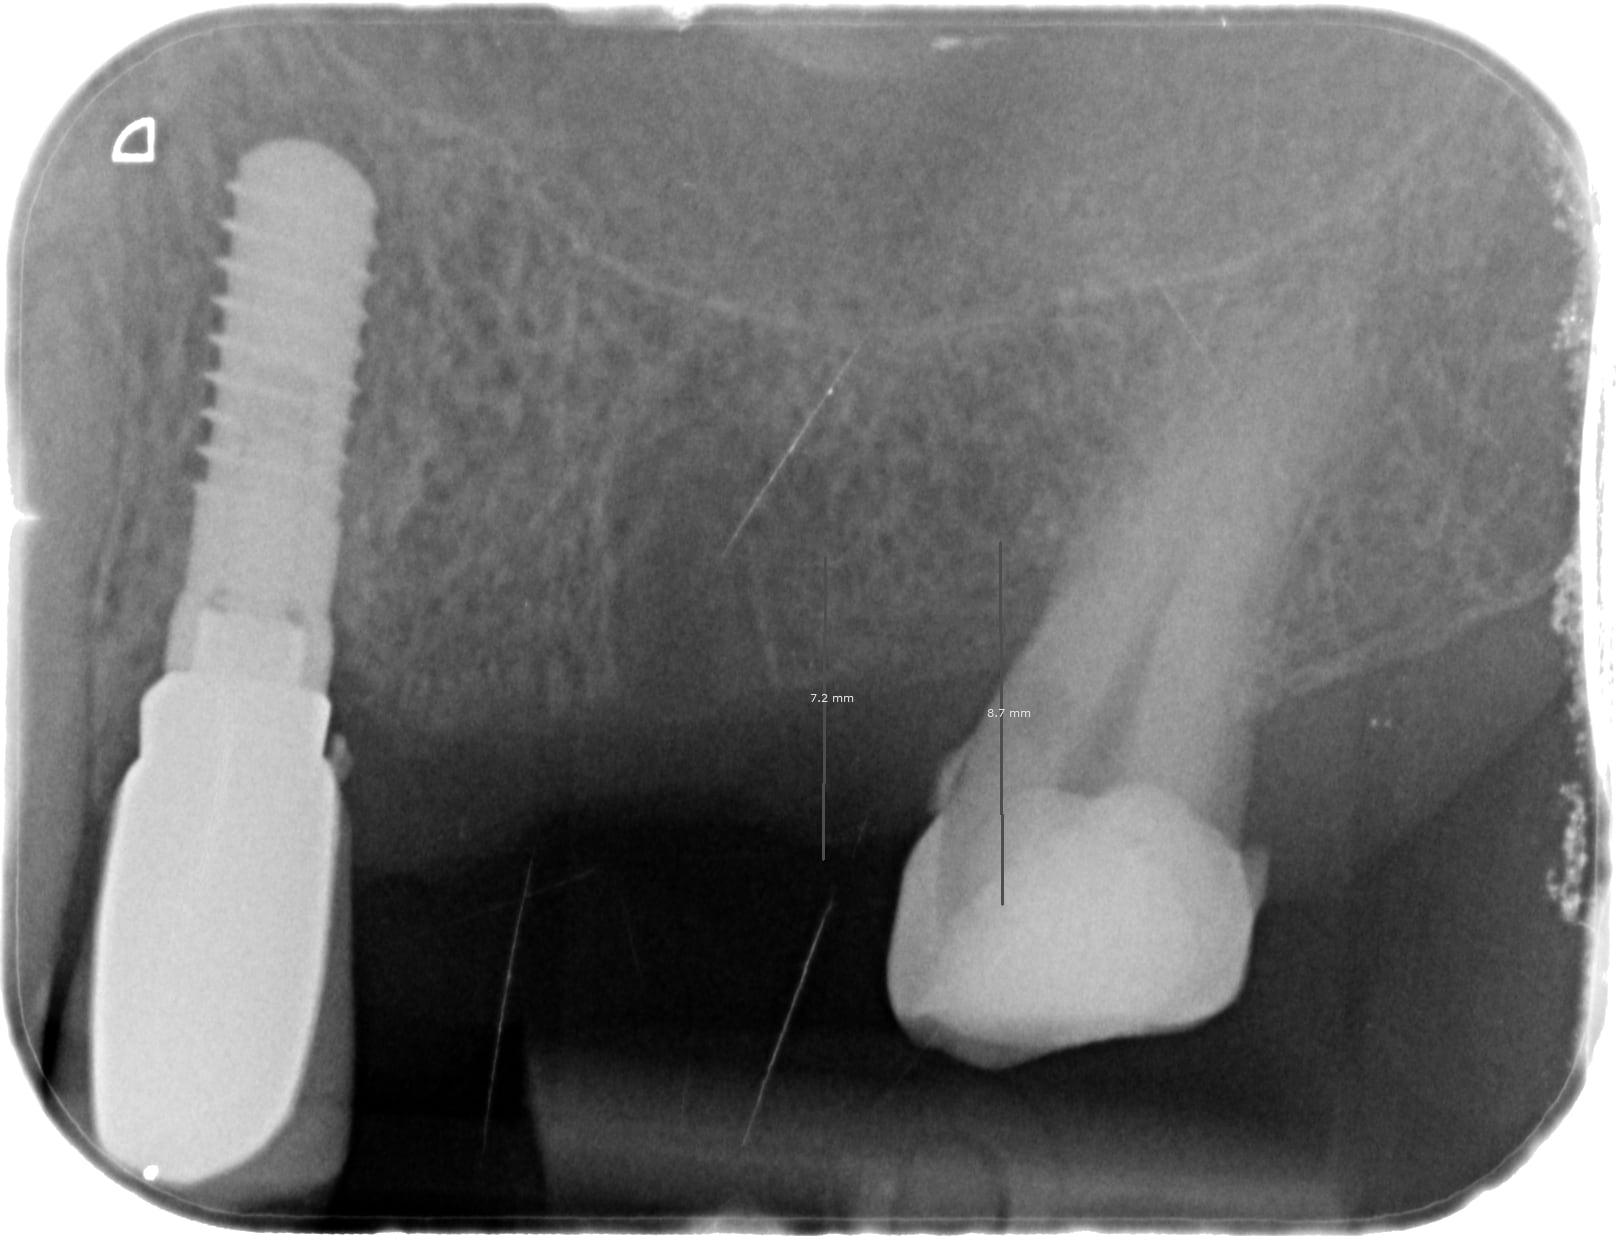

je besoin de votre expertise - moi je suis encore bébéposeur. Un copain de ma femme a perdu une couronne scellé sur implant. C'est le pilier qui c'est dévissé avec l'implant. L'axe de l'implant m'impose une couronne scellé - j'aurais préféré transvissé mais c'est comme ça. Donc bref j'aimerais bien s'avoir quelle marque était posé et voir si il y a des pièces compatibles.

Moi je penche sur une Southern Implants ITC4.1 ; je connais pas du tout cette marque!

c'est un ONB de chez IDI....;-)

ou un IPT Gold....mais c'est la même connexion...il n'y a que le col doré comme différence...